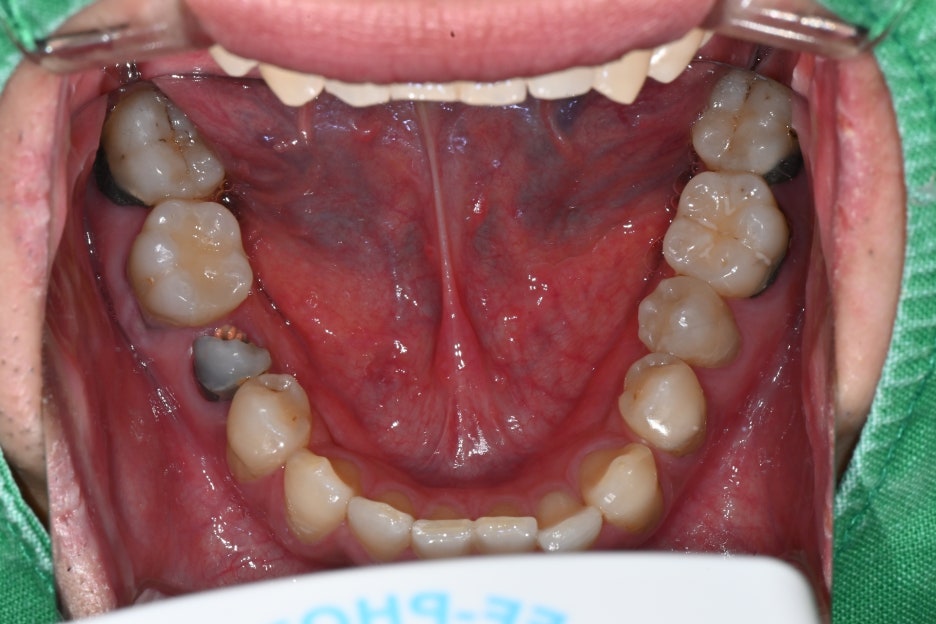

처음 내원 당시 사진

송파구 임플란트